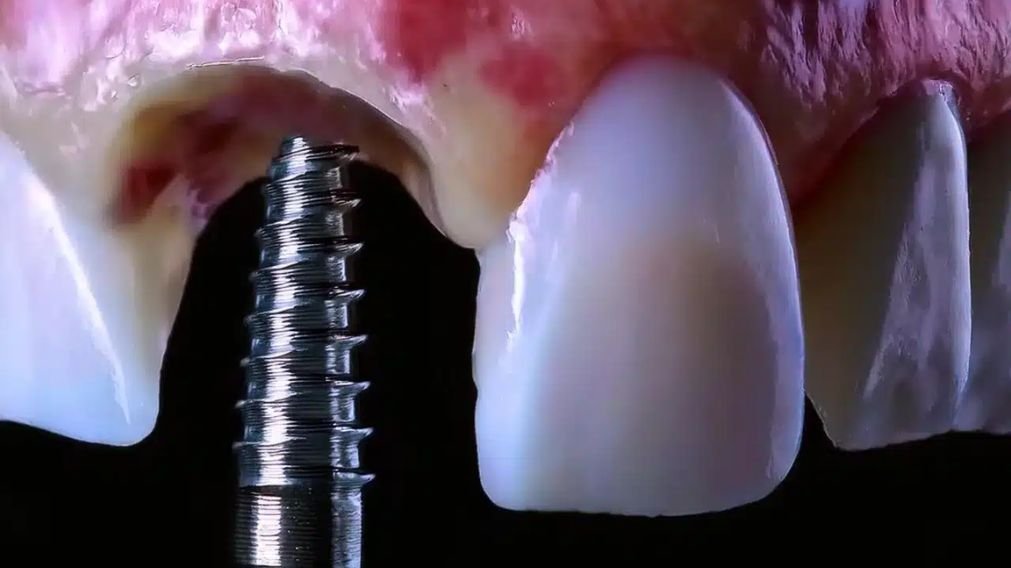

A carga imediata é um procedimento onde uma coroa (dente) provisória fixa é instalada sobre o implante de titânio logo após a sua inserção cirúrgica no osso, geralmente na mesma consulta ou em até 72 horas.

- Carga Imediata (Método Moderno): É como construir uma casa em um terreno de rocha pura. A fundação (implante) fica tão firme e estável desde o início que já é possível erguer uma estrutura temporária (o dente provisório) imediatamente, sem risco de comprometer a base. A casa definitiva (dente de porcelana ou zircônia) será construída alguns meses depois, quando a osseointegração estiver 100% completa.

Importante: O dente instalado no mesmo dia é uma prótese provisória de alta qualidade estética, feita geralmente de resina acrílica. Ela tem a função de devolver a estética, a fala e a mastigação (com cuidado), enquanto o processo de osseointegração ocorre de forma segura. A prótese definitiva, mais resistente e estética, será confeccionada após 3 a 6 meses.

1. Estabilidade Primária Elevada (O Fator Chave)

Este é o critério mais importante. A estabilidade primária é o “aperto” inicial do implante no osso no momento da cirurgia. Medimos essa estabilidade com um torquímetro cirúrgico, em uma unidade chamada Newton por centímetro (Ncm).

- Carga Imediata Segura: Geralmente, um torque de travamento acima de 35-40 Ncm é necessário.

- Carga Tardia Indicada: Torques abaixo de 35 Ncm indicam que é mais seguro aguardar a osseointegração antes de colocar o dente.

Essa firmeza inicial garante que o implante não se mova durante a cicatrização, o que é fatal para a osseointegração.